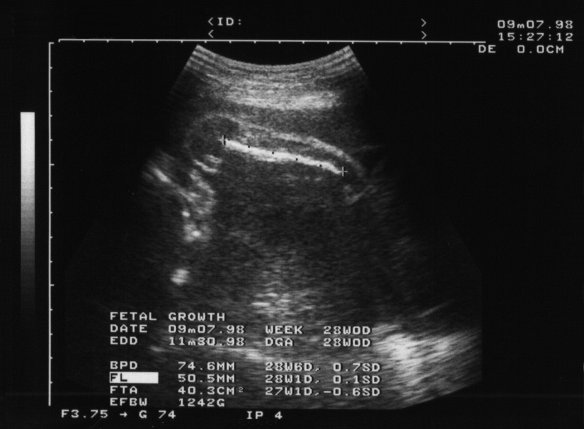

98年9月7日(妊娠29週0日)

「エコー」には入りきらないので,シロウトが見ても分らないらしい. 確かに何が写っているのか分らない. なんでも,大腿骨(いわゆるフトモモ)の長さを計っているそうな.